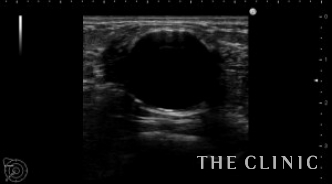

この方は大きなオイルシストと細かい石灰化が混在したしこりでした。

左がオイルシストです。 右は細かい石灰化です。

手で触れる多くのしこりはオイルシストで、細かい石灰化はほとんど触れません。